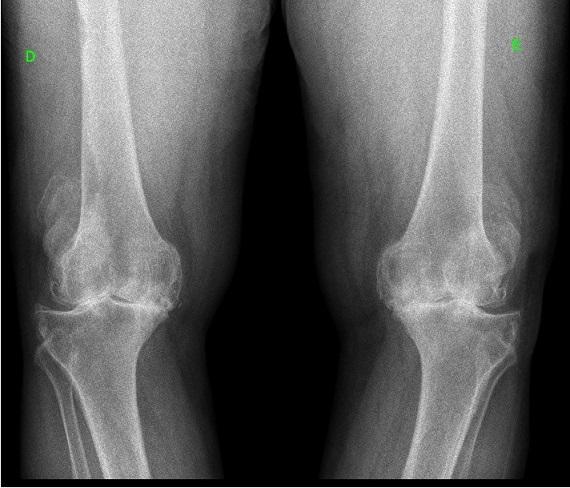

As recomendações para manejo da osteoartrite de joelho a longo prazo ainda são incertas, um estudo recente tentou esclarecer a questão. Confira o resultado: